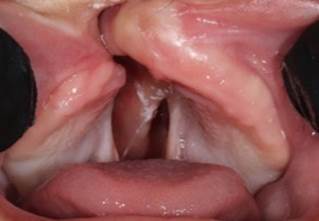

It has a unilateral hard and soft palate fissure, with cleft lip (right side) Figure 1, Figure 2, Figure 3, Figure 4, Figure 5.